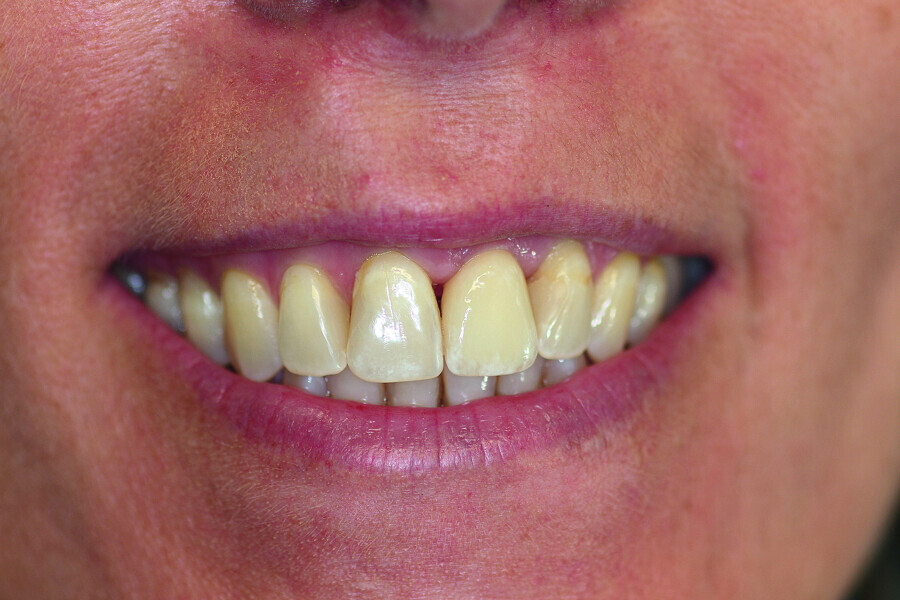

Fig. 11: The final result.